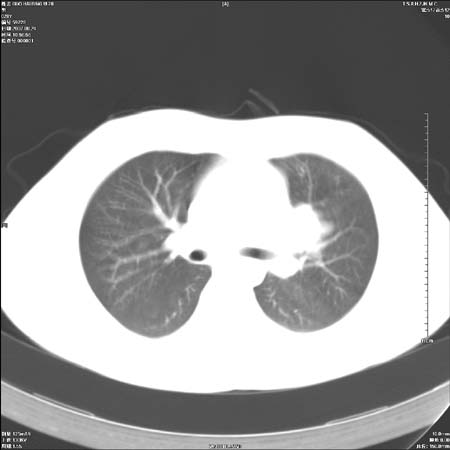

男性,28岁,体检发现左肺病变,患者只有背部隐痛感,哀哉,真不忍心下诊断啊。

左肺门区软组织肿块,左肺上叶支气管开口消失,纵隔内见肿大淋巴结,考虑左中心型肺部,可以做纤支镜取病理确认.

左肺肺门区肿块影,分叶明显:诊断肺癌应该没有疑问。

本例肿块边缘外侧可见左上叶各段支气管。

左肺肺门区肿块影,分叶明显,左肺上叶支气管开口受压,纵隔内见肿大淋巴结,考虑左中心型肺癌。

左侧肺门区见一块状病灶可见分叶,纵隔内及左肺门见肿大淋巴结,应该是周围型肺癌而不是中心型肺癌,原因有以下2点,1未见阻塞肺气肿和阻塞性炎症,这么大肿块如果是中心型肺癌就是未分化型或小细胞型肺癌不出现阻塞性肺不张也应该有阻塞炎症或阻塞性肺气肿,2如果是中心型肺癌临床出现最早的症状是咳嗽(此时可无任何异常影象),而此人这么大肿块只有背部隐痛是体检才发现无法解释.